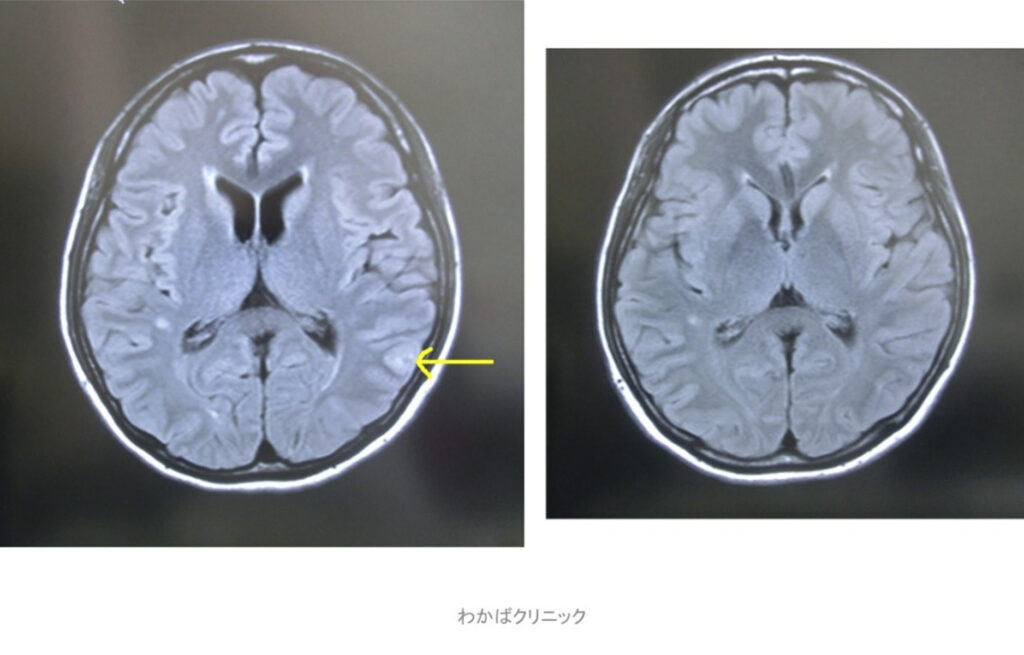

- 西洋医学的な効果判定(必ず必要です)

- CT・MRI・超音波検査 他